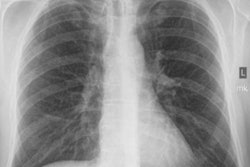

Black lung became such a scourge that in 1969 the U.S. government established the Federal Coal Mine Health and Safety Act, which gave NIOSH the authority to run a screening program to detect early signs of black lung in miners. The program offered chest x-ray screenings to coal workers, with images read by NIOSH-certified physicians, informally called B readers. Miners found to have black lung became eligible to receive disability benefits paid for by their employer.

To analyze the trend in more detail, the NIOSH researchers looked at the prevalence of coal workers' pneumoconiosis on radiographs acquired of workers in underground mines from 1970 to 2017 that were collected as part of the screening program. Coal workers' pneumoconiosis was defined as the presence of small opacities with profusion category of 1/0 or greater on the International Labour Office Classification of Radiographs of Pneumoconioses scale. Progressive massive fibrosis was defined as any large opacity greater than 1 cm.